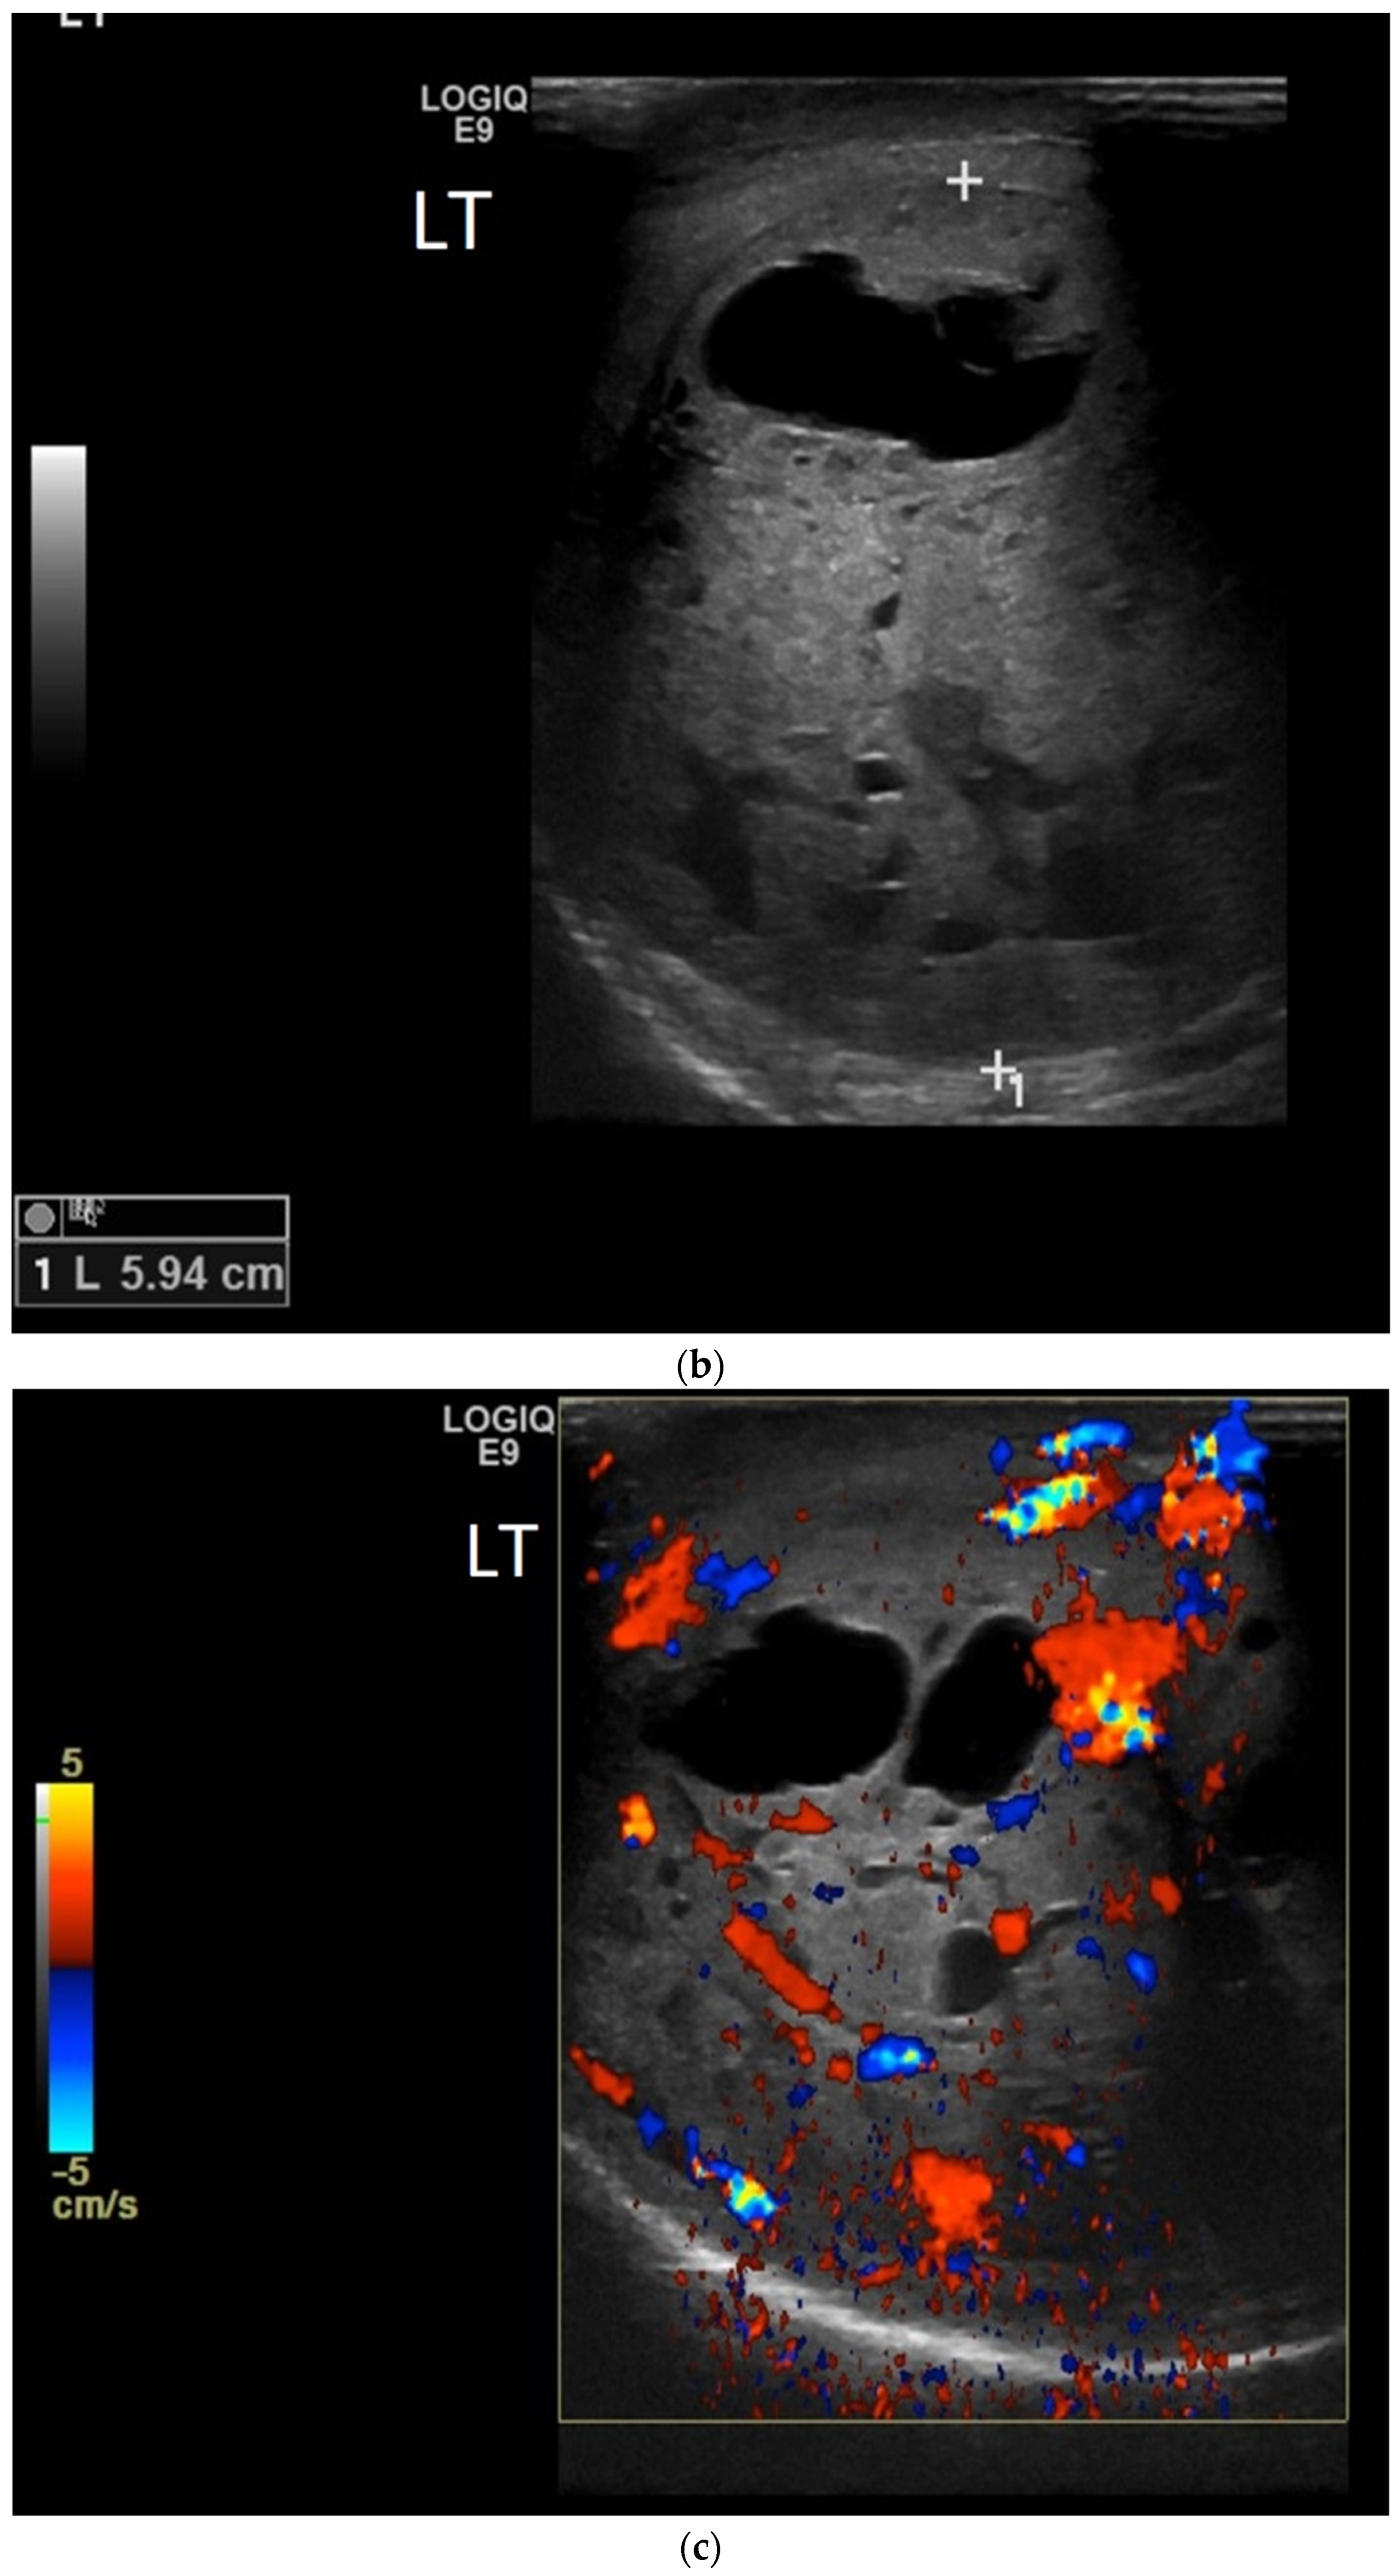

4.1. Seminomatous Germ Cell Tumour

| Seminomas | Homogenous and hypoechoic Well circumscribed Occasionally contain cystic components or calcifications |